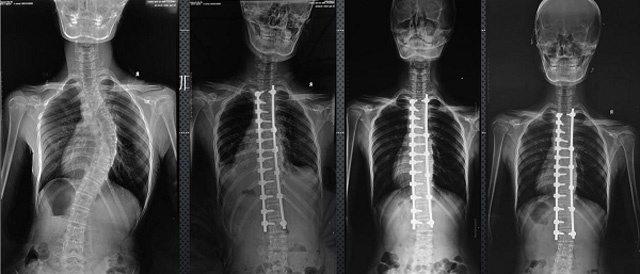

(7)全身拼接功能對有較大尺寸全脊柱拼接圖接桂成金下股分成幾次拍攝,再經(jīng)過秋件開在骨科開展的全脊柱畸形矯治工作中,雖然CT. MRI也能獲取全脊柱影像,接圖像,以便于長度、角度、力線等測量和察脊柱在重力情況下但不能進行立位檢查,無法觀全景觀察。全身拼接功能是高等級DR攝取患者立位全下的功能狀態(tài)圖像,因此采用動態(tài)醫(yī)院特別看重的動態(tài)DR功能之一。注:圖中Cobb脊柱正側位圖像是首選的檢查方法角度的大小是反映側彎嚴重程度的一個標準。